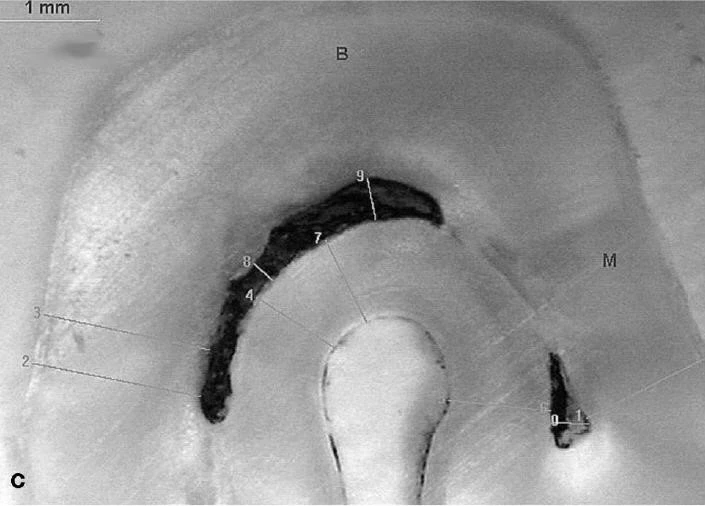

Có nhiều cách phân loại ,nhưng tôi thấy cách phân loại theo Wen Lin Chai,Yo Len Thong thuộc đại học Malaysia đăng trên Journal of Endodontic Vol .30.No .7 ,July 2004 là khá đơn giản ,các tác giả này đã phân CS thành 4 loại :

Theo một khảo sát trên 20 cases CS ,thì tỷ lệ : loại 1 là 27%,2+3 là 64%,loại 4 là 9%. Trong đó 95% là Răng 7 hàm dưới .Theo một số báo cáo khác thì CS cũng gặp trên R6 dưới,R4 dưới,R8 dưới,R6 trên,R7 trên.Lưu ý là phân loại này chỉ tính trên lỗ ống tủy ( orifices) tại sàn buồng tủy chứ còn nếu xuống theo từng lát cắt ngang ( cross – section) thì nó có thể biến từ dạng này sang dạng khác ( khi dính,khi lại tách rời !).

Hình ảnh một ÔT được OB bằng Thermafil+ GP lỏng ( nguồn : GUTMANN).